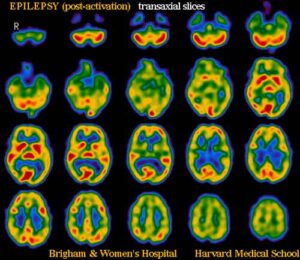

I ricercatori del Cincinnati Children's Hospital hanno scoperto il meccanismo biologico che porta alle convulsioni cerebrali. Lo studio, pubblicato sulla...

Alcuni scienziati del Bernstein Center presso l'Università di Friburgo (Germania) hanno fatto un passo avanti nel tentativo di prevenire le...

Una nuova ricerca ha rivelato che l'epilessia focale si verifica quando le cellule cerebrali chiamate astroglia provocano l'attivazione dei neuroni...

Gli scienziati della University of Iowa ritengono di aver trovato il meccanismo con cui si spiega l’epilessia. Un canale noto...